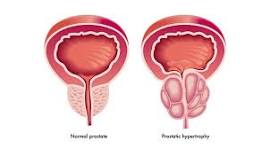

A Força da Detecção Precoce: Câncer de Próstata

O câncer de próstata é o segundo tumor mais comum entre os homens. Nas fases iniciais, a doença costuma ser silenciosa, não apresentando sintomas, o que torna os exames de rotina fundamentais para garantir chances de cura superiores a 90%

Como Proceder: Rastreamento e Diagnóstico

A decisão de realizar exames deve ser individualizada após conversa com um urologista. As recomendações gerais incluem:

- Idade para Iniciar: Geralmente aos 50 anos para homens de risco médio; aos 45 anos para homens da raça negra ou com histórico familiar (pai ou irmão).

- Exames Principais: O PSA (exame de sangue) e o Toque Retal são complementares; um pode detectar o que o outro não revela.

- Confirmação: Caso haja alterações suspeitas, o médico pode solicitar uma Ressonância Magnética e, por fim, uma Biópsia para confirmar o diagnóstico.